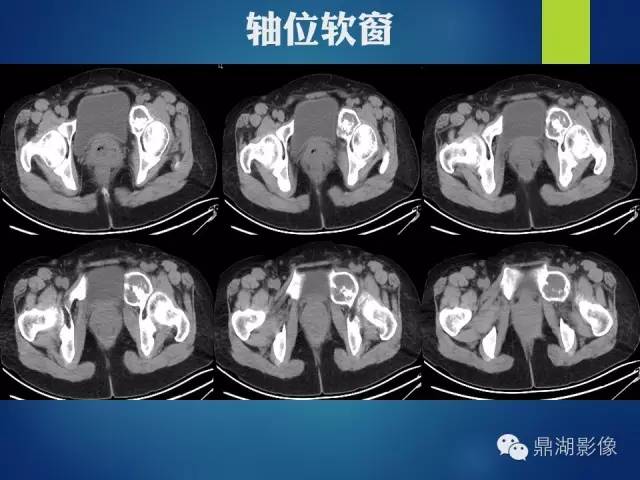

影像表现:

左侧耻骨可见一不规则略低于软组织密度影,周围骨皮质变薄,其内可见丝瓜囊样密度增高影,未见明显骨膜反应及骨折线。

X 线表现为侵蚀骨质破坏,可见软组织肿块。CT 能更清楚地显示其钙化,但不广泛。肿块含水量多,故在CT像上表现为低密度;黏液型软骨肉瘤较普通型软骨肉瘤更常见出血,在MRI的T1WI、T2WI 上均表现为高信号, (肿块) 增强扫描肿块呈轻度强化。